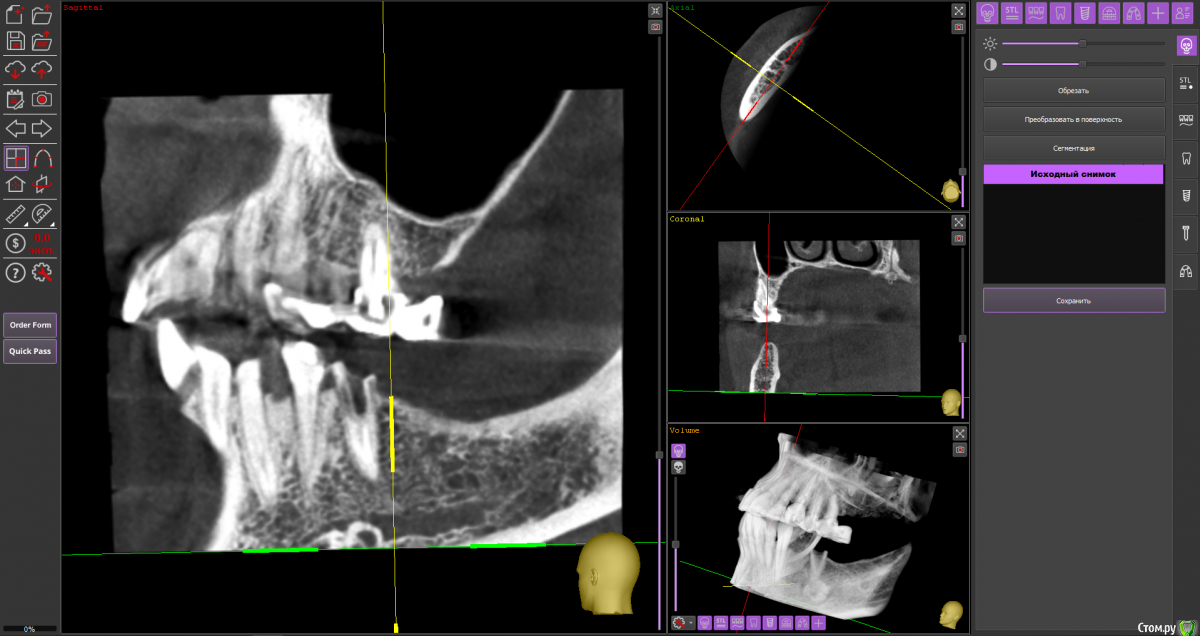

Fin Опубликовано 6 мая, 2020 Поделиться Опубликовано 6 мая, 2020 Здравствуйте коллеги. Пришла пациентка, для установки импланта в обл 3.6. После осмотра КТ обнаружил образование в проекции будущего импланта. В ходе осмотра КТ так же обнаружилось несколько подобных образований по НЧ. Помогите советом, кто сталкивался с подобной ситуацией и что это может быть? Ссылка на комментарий

Дмитрий Л. Опубликовано 6 мая, 2020 Поделиться Опубликовано 6 мая, 2020 Ну сделайте трепан биопсию. Через пару недель можно будет и имплант вкрутить. Я думаю что это костный рисунок. Ссылка на комментарий

wladdX Опубликовано 6 мая, 2020 Поделиться Опубликовано 6 мая, 2020 (изменено) Мне тоже кажется, что вы принимаете балочную структуру и петли н\ч канала за н\образование. Такое встречается иногда. Похожий случай На ОПТГ выглядит уже не так трагично Изменено 6 мая, 2020 пользователем wladdX 1 Ссылка на комментарий

It'sGeorgy Опубликовано 6 мая, 2020 Поделиться Опубликовано 6 мая, 2020 Тоже часто сталкиваюсь с таким. Костный рисунок. 1 Ссылка на комментарий

Fin Опубликовано 7 мая, 2020 Автор Поделиться Опубликовано 7 мая, 2020 Мне тоже кажется, что вы принимаете балочную структуру и петли н\ч канала за н\образование. Такое встречается иногда. Похожий случай46_1.jpg На ОПТГ выглядит уже не так трагичноОПТГ фрагмент.jpgЧестно говоря тоже думаю, что костный рисунок но смутили размеры и то что в других местах кроме этих таких явлений не наблюдается. Сейчас пациент предоставил снимок до ортод. лечения. На нем немного видно костный рисунок. Ссылка на комментарий

Fin Опубликовано 7 мая, 2020 Автор Поделиться Опубликовано 7 мая, 2020 Тоже часто сталкиваюсь с таким. Костный рисунок.Извините, хотел нажать кнопку ответа а поставил минус((.Такое тоже вижу очень часто, но смущают размеры. Ссылка на комментарий